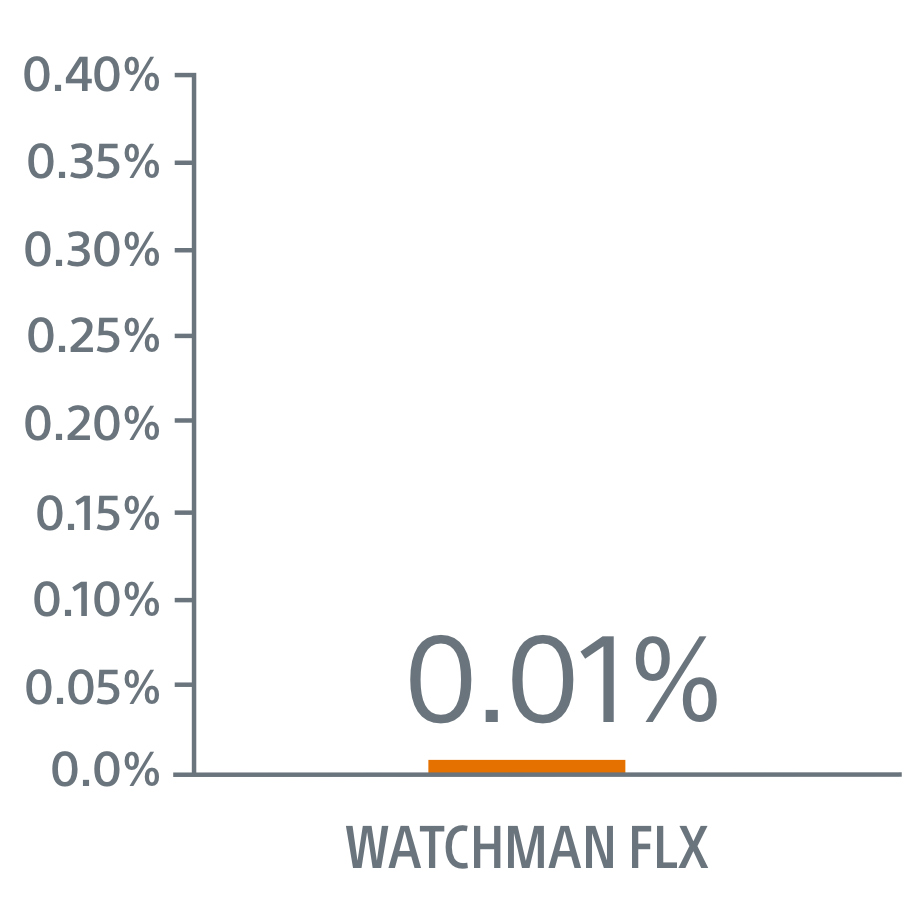

- WATCHMAN FLX superior on clinically relevant pericardial effusion/tamponade (0.01% FLX vs 0.7% Amulet, p=0.01)

Seal

WATCHMAN FLX showed a trend towards more frequent appendage occlusion (leaks >5mm; p=0.06). WATCHMAN FLX demonstrated fewer peri-device leaks >5mm than Amulet (0.01% vs 0.34%, p=0.06)